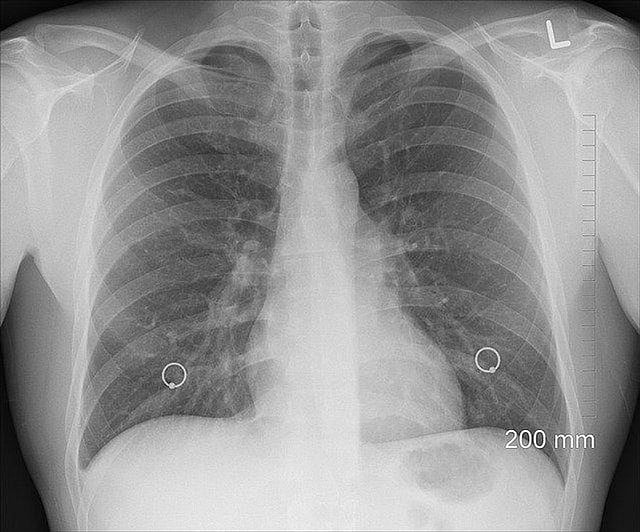

Your lungs can smell. That's what new research suggests. But unlike the odor receptors in your nose, which send a message to the brain, the receptors in your lung cause the airways to constrict when a pungent or caustic odor such as cigarette smoke is sensed. The new class of cells called pulmonary neuroendocrine cells, or PNECs, were discovered by scientists at Washington University in St. Louis and the University of Iowa.

The researchers say the cells might be responsible for the chemical hypersensitivity that characterizes respiratory diseases, such as chronic obstructive pulmonary disease (COPD) and asthma. Patients with these diseases are told to avoid traffic fumes, pungent odors, perfumes, and similar irritants, which can trigger airway constriction and breathing difficulties.

In 2009, Ben-Shahar found that ciliated cells, cells with tiny hairlike protuberances that are responsible for moving things in the airway, responding to bitterness. But since people are sensitive to many inhaled substances, not just bitter ones, he wanted to revisit the issue. This time, he found that these tissues also express odor receptors, not on ciliated cells but instead on neuroendocrine cells, flask-shaped cells that dump serotonin and various neuropeptides when they are stimulated.

Cells in the airways are secretory, not neuronal, cells, and they may carry more than one receptor, so they are broadly tuned. Instead of sending nerve impulses to the brain, they flood local nerves and muscles with serotonin and neuropeptides. "They are possibly designed," he said, "to elicit a rapid, physiological response if you inhale something that is bad for you."

When the scientists looked at the airway tissues from patients with COPD, they discovered that they had more of these neurosecretory cells than airway tissues from healthy donors. Ben-Shahar is hopeful that the PNEC pathways will provide targets for drugs that would better control asthma, COPD, and other respiratory diseases. They would be welcome. There has been a steep rise in these diseases in the past few decades, treatment options have been limited, and there are no cures. (VOA/JC)